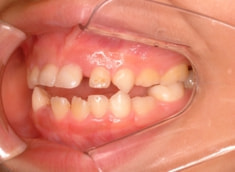

治療後(1年5ヶ月後)

治療開始から11ヶ月